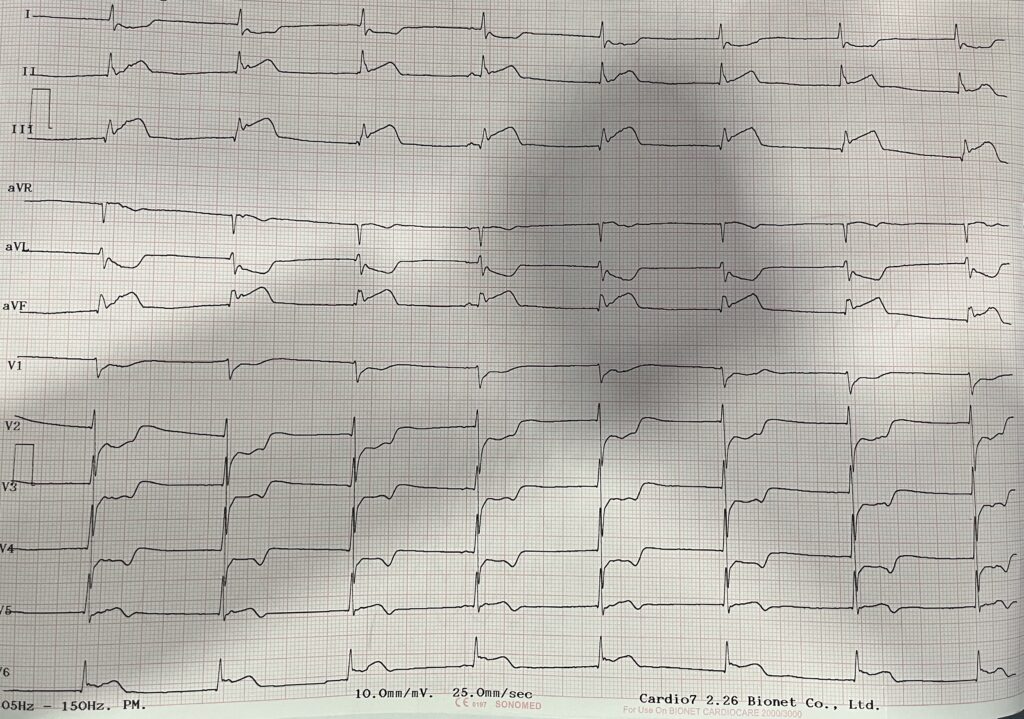

Mujer de 64 años sin Historia Cardiovascular (HCV) y sin Factores de Riesgo Cardiovascular (FRCV) conocidos. Inicia ejercicio a las 7:00 horas y a los pocos minutos presenta dolor precordial de perfil isquémico. Fue valorada por médico particular quien refiere con cardiólogo, el cual realiza electrocardiograma (ECG) de 12 derivaciones en el que observa elevación del segmento ST en derivaciones de la cara inferior (DII, DIII y aVF) y lateral baja (V5-V6), desnivel negativo del segmento ST en derivaciones de la cara anterior (V1-V4) y lateral alta (DI y aVL), con ritmo nodal y FC estimada en 48 lpm, por lo cual se traslada a la institución en ambulancia.